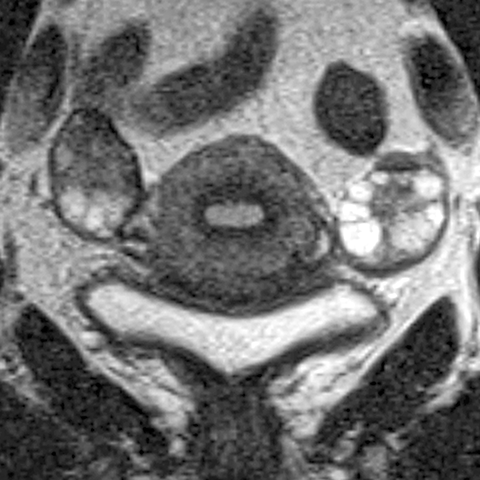

Ovary (T2 weighted MR, coronal) [3 of 4]